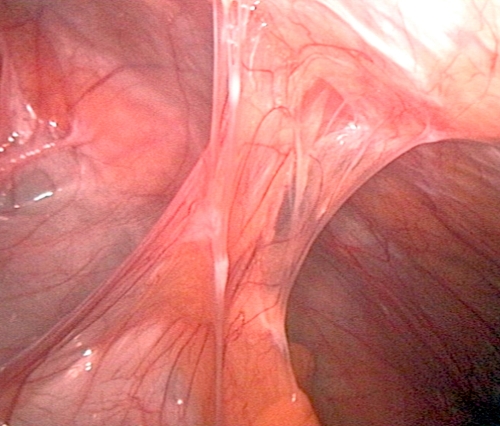

內視鏡影像展示,纖維化沾黏(Fibrous Adhesions)形成的索帶結構,如同纜繩般,將淺層組織緊緊拴住在深層結構,造成抽脂術後的外觀凹陷。如果未先處理這些高張力的纖維束,任何填充物都會被迫流向低阻力區。

針對纖維化沾黏,首要步驟為物理性的空間釋放。傳統管徑(>3mm)較粗,操作鈍力大,易造成廣泛性組織破壞與出血,增加血清腫與血腫風險。顯微套管<2.2mm的極細小管徑,具備以下優勢:

此步驟的重點在「皮下鬆解」,顯微套管就像一把精細的繡花針,我們透過多層次扇形分離手法,不僅可以精準地切斷將皮膚往下拉的纖維束,同時在皮下脂肪層與淺層筋膜間創造出受區囊袋,將原本沾黏的疤痕組織,轉化為可容納填充的疏鬆空間,降低後續填充時的組織對抗壓力。